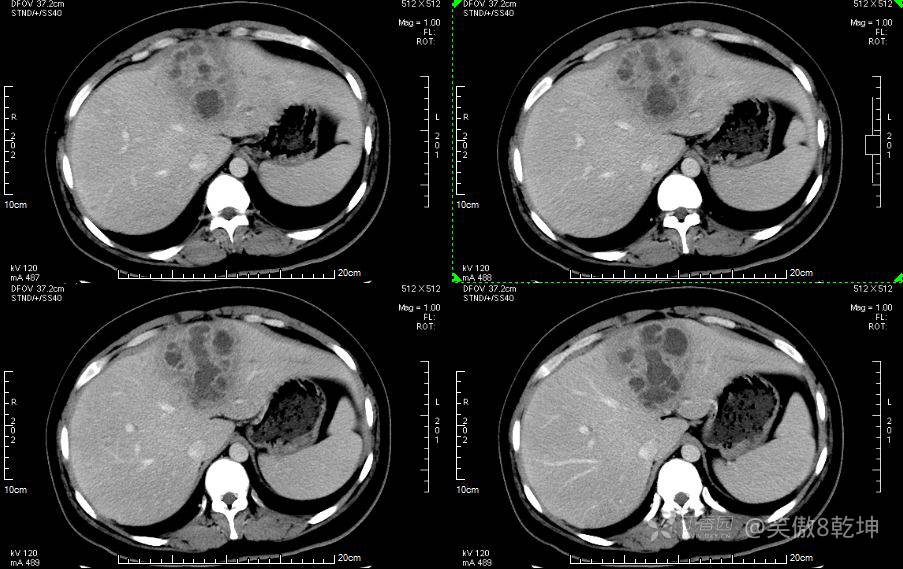

诊断似乎倾向于肝脓肿了,与患者或家属沟通后完善上腹部强化CT:

证实为肝脓肿,至此,诊断思路似乎清晰起来,患者血糖的升高使得微小血管容易出现循环障碍,同时白细胞的吞噬能力及抗感染能力下降,所有易出现感染性疾病。而肝脓肿通常不容易早期发现。患者的年龄同时让临床医生不容易想到此诊断。